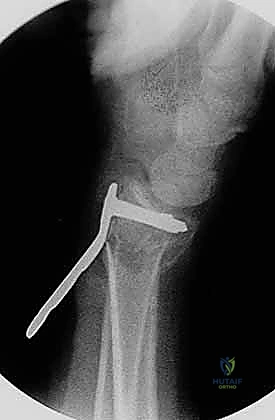

4. وضع الصفيحة والتثبيت المؤقت

يتم اختيار صفيحة تيتانيوم مصممة تشريحياً لتلائم انحناء الكعبرة. توضع الصفيحة على العظم وتُثبت مؤقتاً بأسلاك معدنية دقيقة (K-wires).

5. حفر العظم ووضع المسامير

يتم حفر ثقوب في العظم عبر فتحات الصفيحة، ثم تُقاس المسافات بدقة لإدخال مسامير القفل (Locking Screws) في الجزء البعيد (قرب المفصل) ومسامير قشرية في الجزء القريب (في ساق العظم).

6. الفحص النهائي والإغلاق

يتم إجراء فحص أخير بالأشعة للتأكد من المحاذاة المثالية للكسر وأطوال المسامير (لضمان عدم بروزها واحتكاكها بالأوتار الخلفية). بعد ذلك، يتم خياطة الأنسجة والجلد بخيوط تجميلية ووضع ضمادة معقمة.